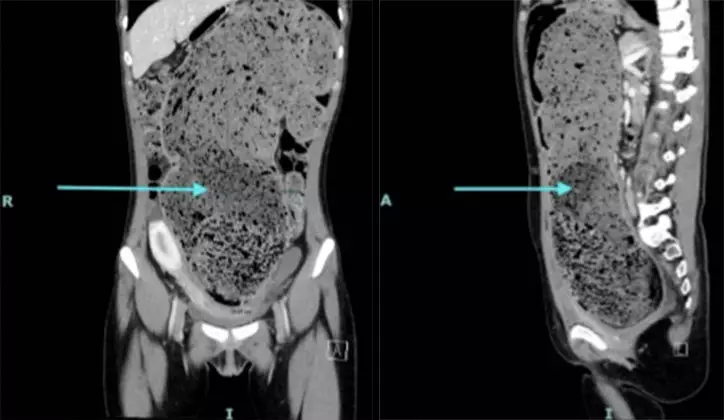

Kasus tersebut kemudian ditangani tim medis yang menemukan usus besar pasien memiliki ukuran abnormal. Ususnya melebar hingga 15 sentimeter dan penuh dengan tinja yang sudah lama mengeras.

Temuan medis itu dicatat dalam laporan yang dipublikasikan di jurnal Cureus. Dokter menggambarkan betapa sulitnya melakukan tindakan pemeriksaan karena tinja pasien terlalu padat dan keras.

Kondisi pasien membuat ususnya terlihat membesar secara signifikan. Dokter menggambarkan tekstur tinja yang dikeluarkan menyerupai tanah liat basah dan padat.

"Dokter mencatat usus besarnya mengalami pelebaran yang signifikan dan tinjanya menyerupai tanah liat yang padat/basah," imbuhnya.